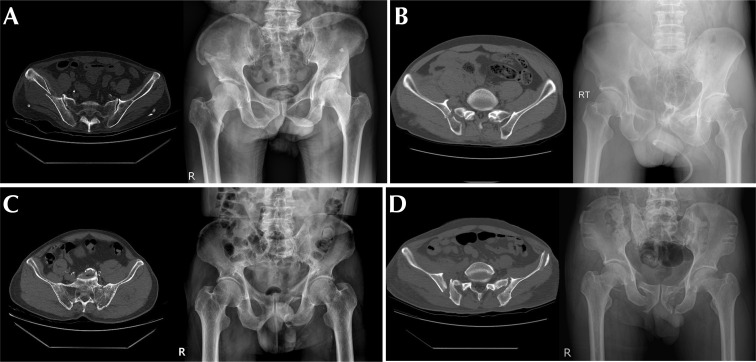

Materials and methods: A retrospective analysis was conducted on 272 patients diagnosed with pelvic ring injuries between January 2004 and October 2023. Patients were categorized into non-ankylosed (n=185) and ankylosed (n=87) SIJ cohorts. The prevalence of SIJ ankylosis in our study sample was 32.0% (87/272). Patient demographics, SIJ ankylosis, PL, and fracture classification using computed tomography were compared between the two groups. PL was defined as any type of posterior ring injury with fracture lines extending to the region posterior to the iliac pillar, with or without SIJ subluxation or dislocation. To determine the association between SIJ ankylosis and PL, a logistic regression analysis adjusted for age, body mass index, sex, and energy of injury mechanism was performed.

Abstract Image